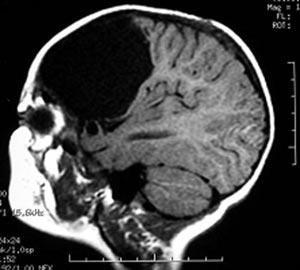

Figura 46 - Ressonância nuclear magnética antes da cirurgia

Figura 48 - Ressonância nuclear magnética realizada 3 meses após a cirurgia mostrando remoção adequada da lesão. Esse paciente apresentava crises desde seu nascimento havia 30 anos. Foi operado em 2003 e permaneceu sem crises desde então.